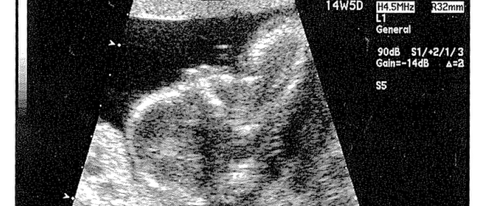

…Only far, far bundle-of-joy-ier. (Click the image for the full size scanination)

We’re due March 17th — that’s right, a St. Patty’s Day baby. They’ll still wear orange, though. *grin*